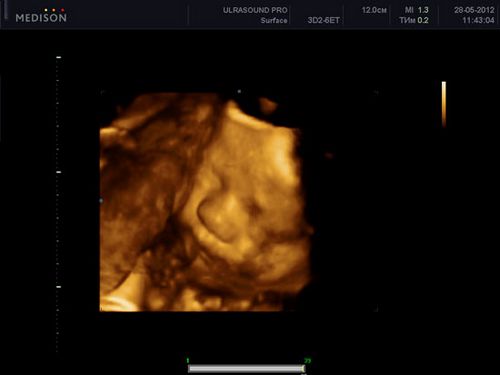

При УЗД плоду в 34 тижні вагітності його вага становить в середньому 2250 г, а зріст 34 см від верхівки до куприка.

Легені плоду вже практично повністю зрілі і готові для першого подиху. При УЗД плоду в 34 тижні вагітності визначити зрілість легеневої тканини можна, якщо порівняти легкі з печінкою плода. Якщо з яких-небудь причин малюк народиться зараз, у нього практично все готово до життя поза маткою. Такі діти зазвичай не потребують інтенсивної терапії (реанімації), можуть самостійно дихати з мінімальною підтримкою кисню. Таких діток зазвичай містять в спеціальних ліжечках з підігрівом. Процеси формування підшкірного жиру ще не закінчилися, тому теплорегуляційні процеси у такого новонародженого можуть страждати.

При УЗД плоду в 34 тижні вагітності позиція плода в 99% випадків відповідає такий при майбутні пологи. Лікар при проведенні УЗД плоду в 34 тижні вагітності повідомить вам, як розташований дитина: головкою вниз або сідницями. У рідкісних випадку можливо поперечне положення плода. При поперечному положенні плода пологи через природні родові шляхи практично не можливі, вони поєднані з високим ризиком для дитини і мами, тому вам запропонують планове кесарів розтин. При сідничному передлежанні можливість народжувати через природні родові шляхи є, особливо якщо це другі (і наступні) пологи.

Фетометрія (розміри плода) при УЗД плоду в 34 тижні вагітності в нормі:

- БПР (біпаріетальний розмір). При УЗД плоду в 34 тижні вагітності біпаріетальний розмір становить 79-93мм.

- ЛЗ (лобно-потиличний розмір). При УЗД плоду в 34 тижні вагітності 101-119мм.

- ОГ (окружність голівки плоду). При УЗД плоду в 34 тижні вагітності окружність голівки відповідає 295-339 мм.

- ОЖ (окружність живота плода) - при УЗД плоду в 34 тижні вагітності становить 276 -336 мм.

Нормальні розміри довгих кісток при УЗД плоду в 34 тижні вагітності:

- Стегнова кістка 60-70мм,

- Плечова кістка 55-65мм,

- Кістки передпліччя 48-56мм,

- Кістки гомілки 55-63мм.